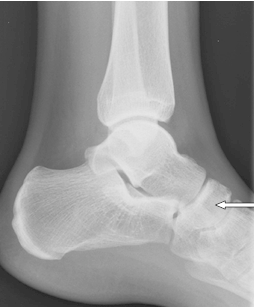

Na radiogramie strzałką oznaczono

A. staw skokowo-piętowy.

B. kość sześcienną.

C. głowę kości skokowej.

D. kość łódkowatą.